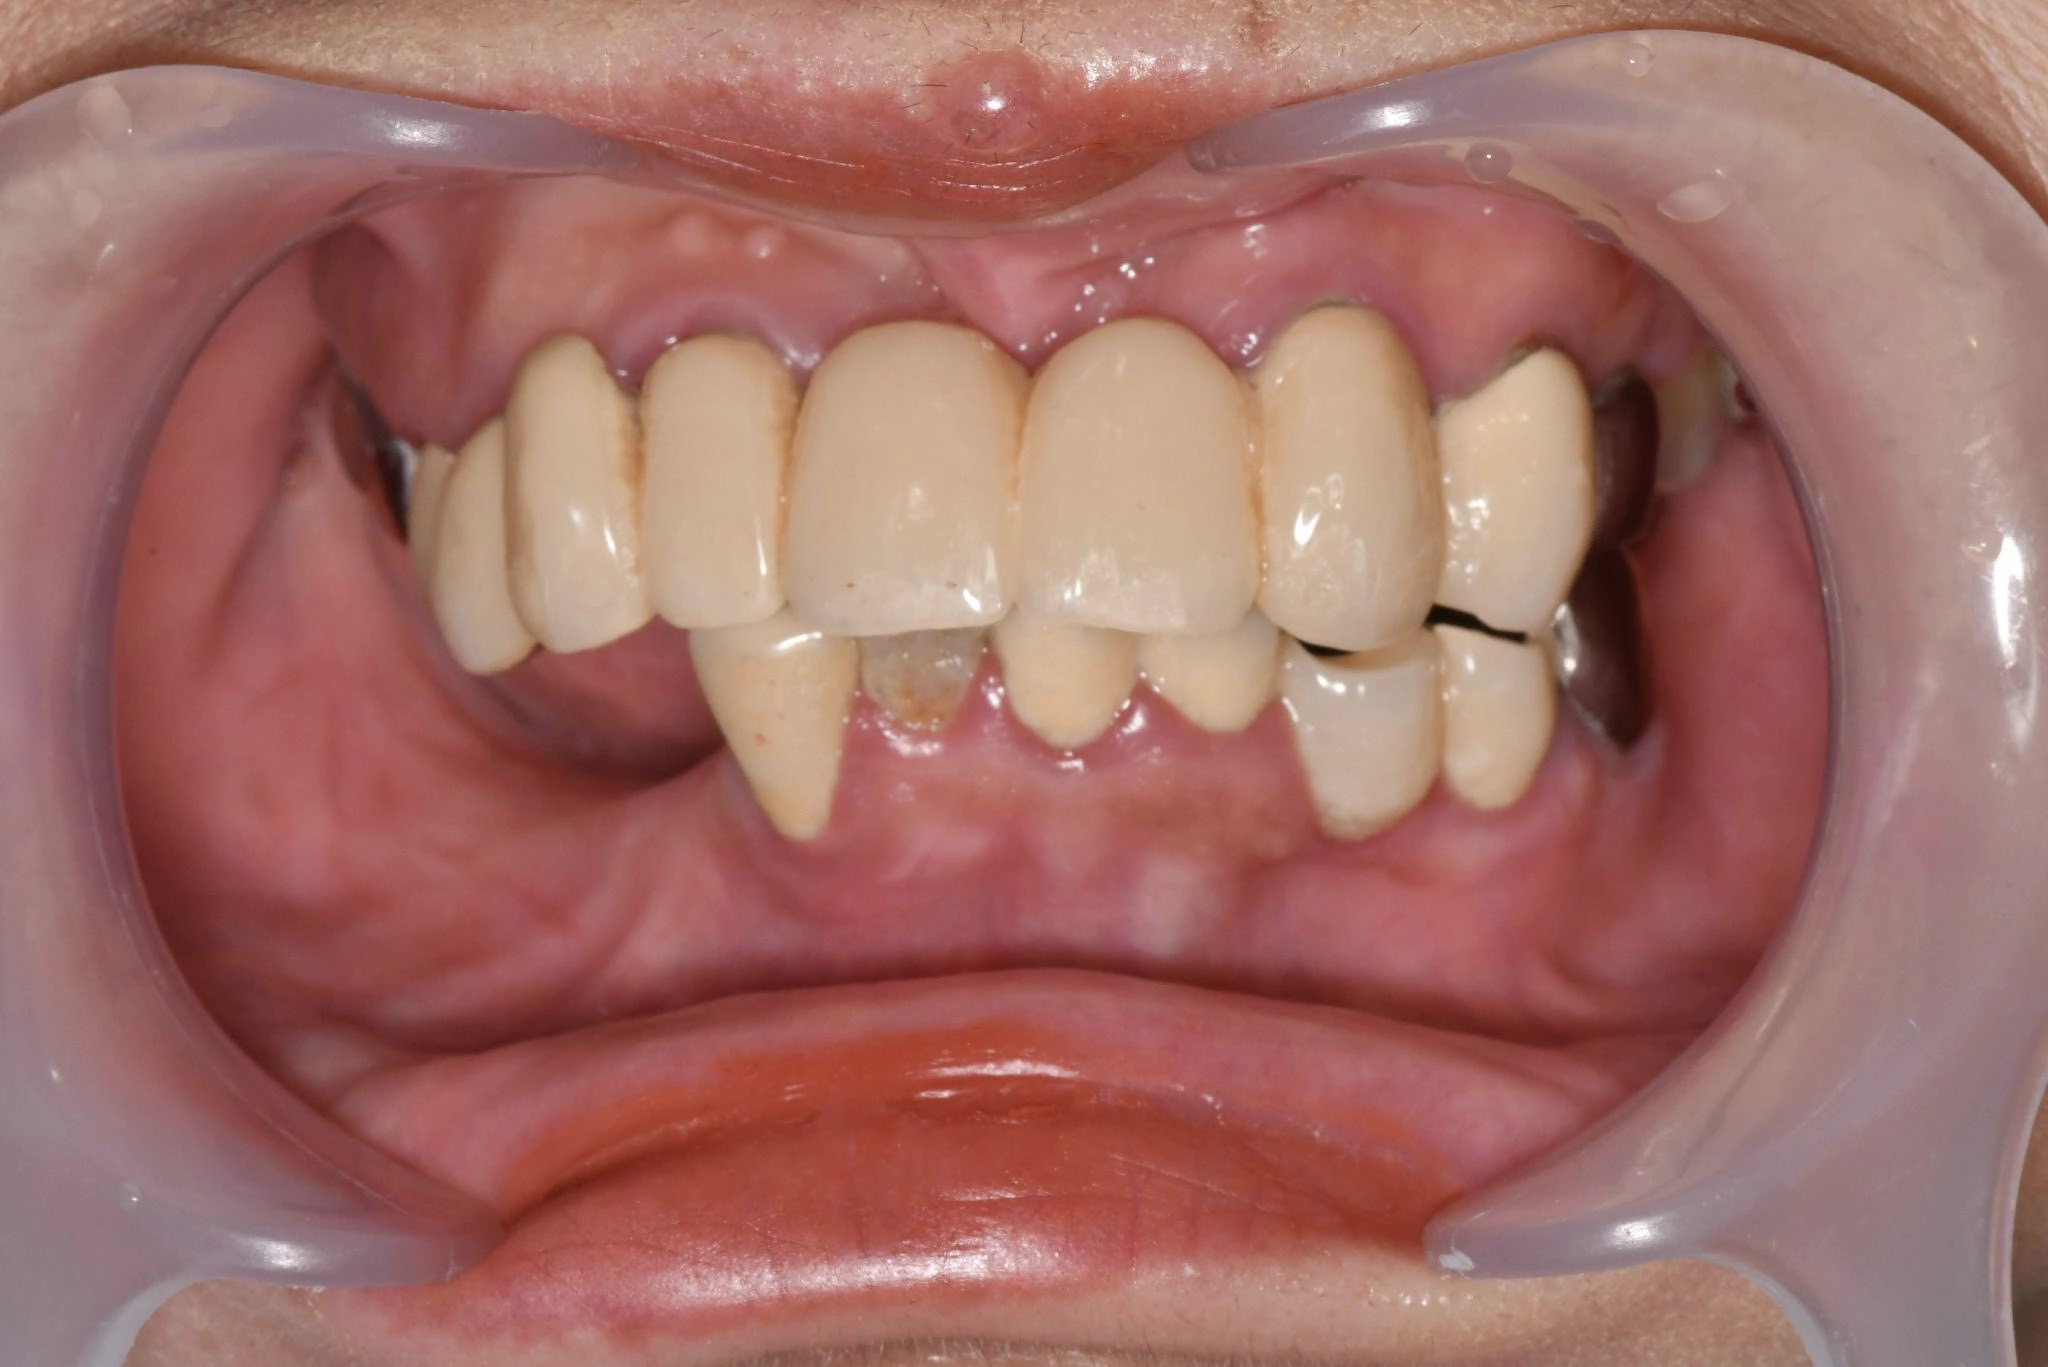

術後

内容 :上下顎オールオン4ザイゴマ2

費用 :4,963,200円

※モニター価格

期間 :半年

リスク:出血・腫れ・痺れ・痛み

他院でインプラント治療を行っていましたが突然閉院となり、治療が中断されてしまいました。噛み合わせや歯並びに深刻な悩みを抱えることになり、口元の不安が負担になっていました。

相談の中でわずか1日で固定式の歯が入るスピード感に大きな魅力を感じました。

「ここなら長年の悩みが無くなるかもしれない」と感じ、手術を受ける決断をしました。

手術当日に歯が入り、その即時性に深く満足しています。これまでは人前で笑えないことが最大の悩みでしたが、これからは笑顔が増えていきそうです。